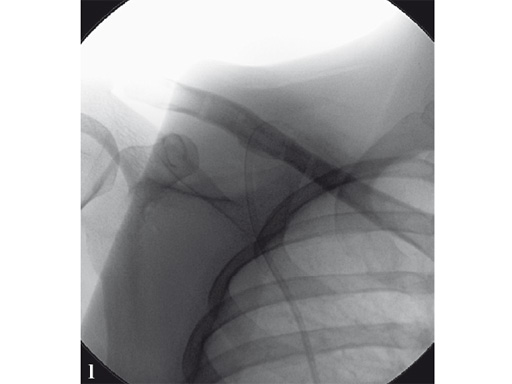

Case 2: a 29-year-old man sustained a midshaft clavicle fracture while playing soccer.

Case provided by Norbert Sdkamp and Martin Jaeger, Freiburg, Germany